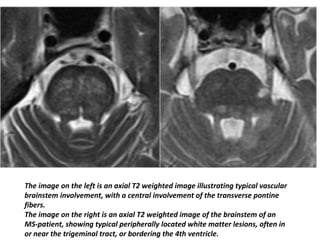

The image on the left is an axial T2 weighted image illustrating typical vascular

brainstem involvement, with a central involvement of the transverse pontine

fibers.

The image on the right is an axial T2 weighted image of the brainstem of an

MS-patient, showing typical peripherally located white matter lesions, often in

or near the trigeminal tract, or bordering the 4th ventricle.